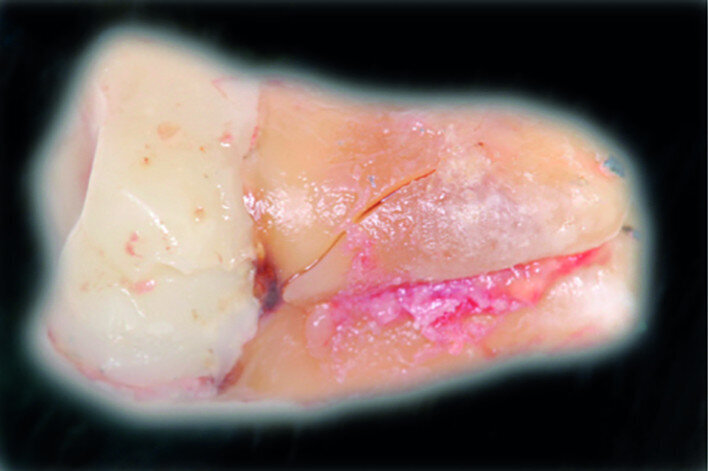

Fig. 12: Pulp chamber floor perforation, immediately after extraction.

Fig. 13: Pulp chamber floor perforation, tooth cleaned.

After local anaesthesia with 2 per cent mepivacaine with 1:100,000 adrenaline, the right maxillary second molar was atraumatically extracted. Initially with a size 15c surgical blade, the periotomy was realised and then the tooth was extracted after separating the roots to avoid unnecessary trauma to the alveolar bone. Then the donor right maxillary third molar was extracted after periotomy as described and transplanted into the adjacent site. Because of the slight differences in the root anatomy, it was necessary to remove the intraradicular bone septum of the receiving site to al- low tooth positioning, and a odontoplastic of the donor tooth crown was performed to maintain it not in occlusion. An antibiotic (amoxicillin/clavulanic acid, 1 g, by mouth twice a day for five days) was prescribed, along with rinses with 0.2 per cent chlorhexidine. The tooth was keep stable with sutures (Fig. 8). A periapical radiograph was taken (Fig. 9). At the suture removal at two weeks, the tooth showed good stability, and positive adaptation of the soft tissue was observed (Fig. 10). At four weeks, the tooth was stable and the soft tissue looked healthy (Fig. 11). The patient did not show any adverse effects and stated that the tooth was fully functional. Examination of the avulsed second molar showed the extent of the perforation (Figs. 12 & 13).